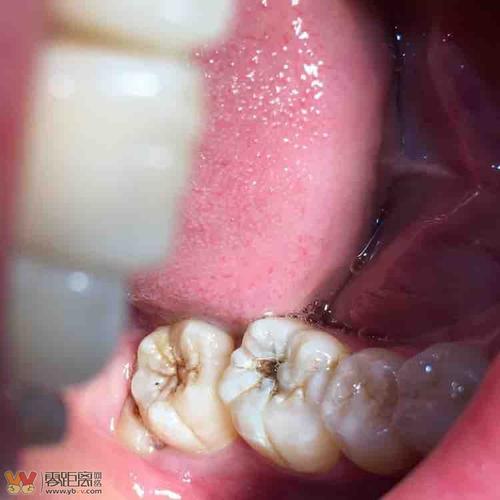

后槽牙牙齿发黑图片,牙齿凹槽上面有黑色

求救前辈们!后槽牙蛀空,填补物脱落,18号才能看上,现在疼到升天.

牙齿表面黑色的点或线段就是窝沟龋啦

最里面的大牙发黑图片

后槽牙牙缝发黑但不疼